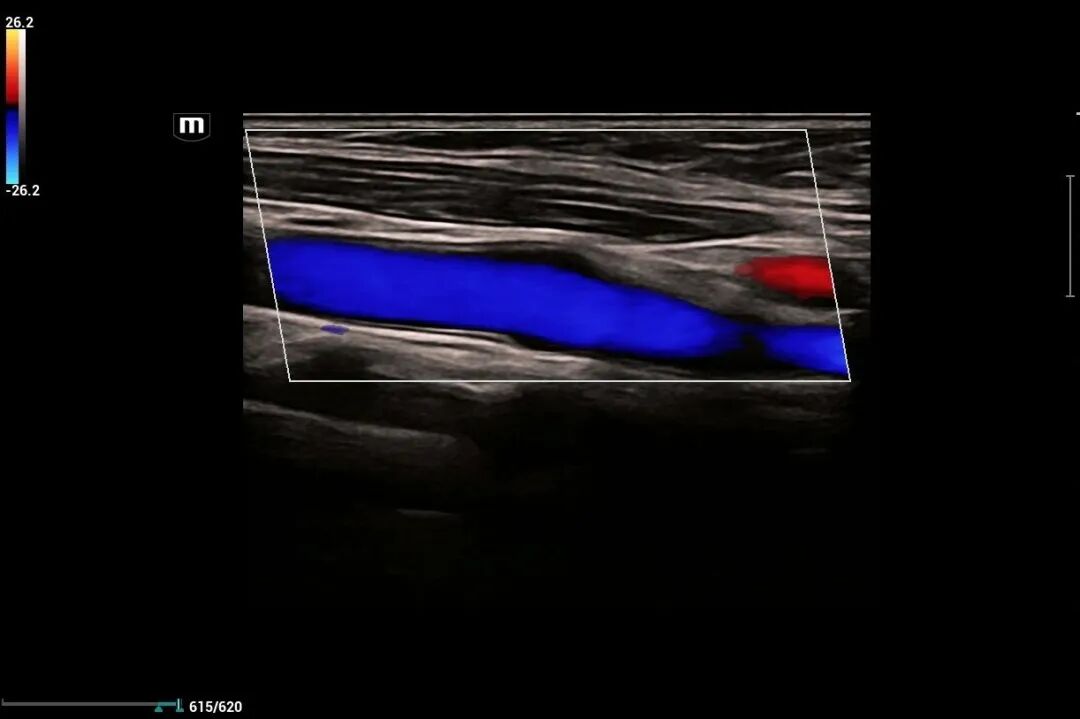

为进一步提高我院诊疗检查与诊断水平,不断满足城乡患者日益增长的就医需求,健全和完善医疗保障体系。2022年12月我院引进了mindray- Resonal9T高端彩色多普勒超声系统正式投入使用,此设备具备超声介入、超声造影、超声高帧率 STE 剪切波弹性成像及应变式弹性成像(甲状腺、乳腺、肝脏),二维、三维、四维、阴式、盆底、心脏及血管超声等功能。此设备的引进标志着海伦影像学科将跨越新的高度,以此助力城乡百姓解决看病难,看病贵的就医难题!

2.肢体血管。如上、下肢动脉,深浅静脉检查;动静脉炎、动脉硬化、动静脉栓塞等。